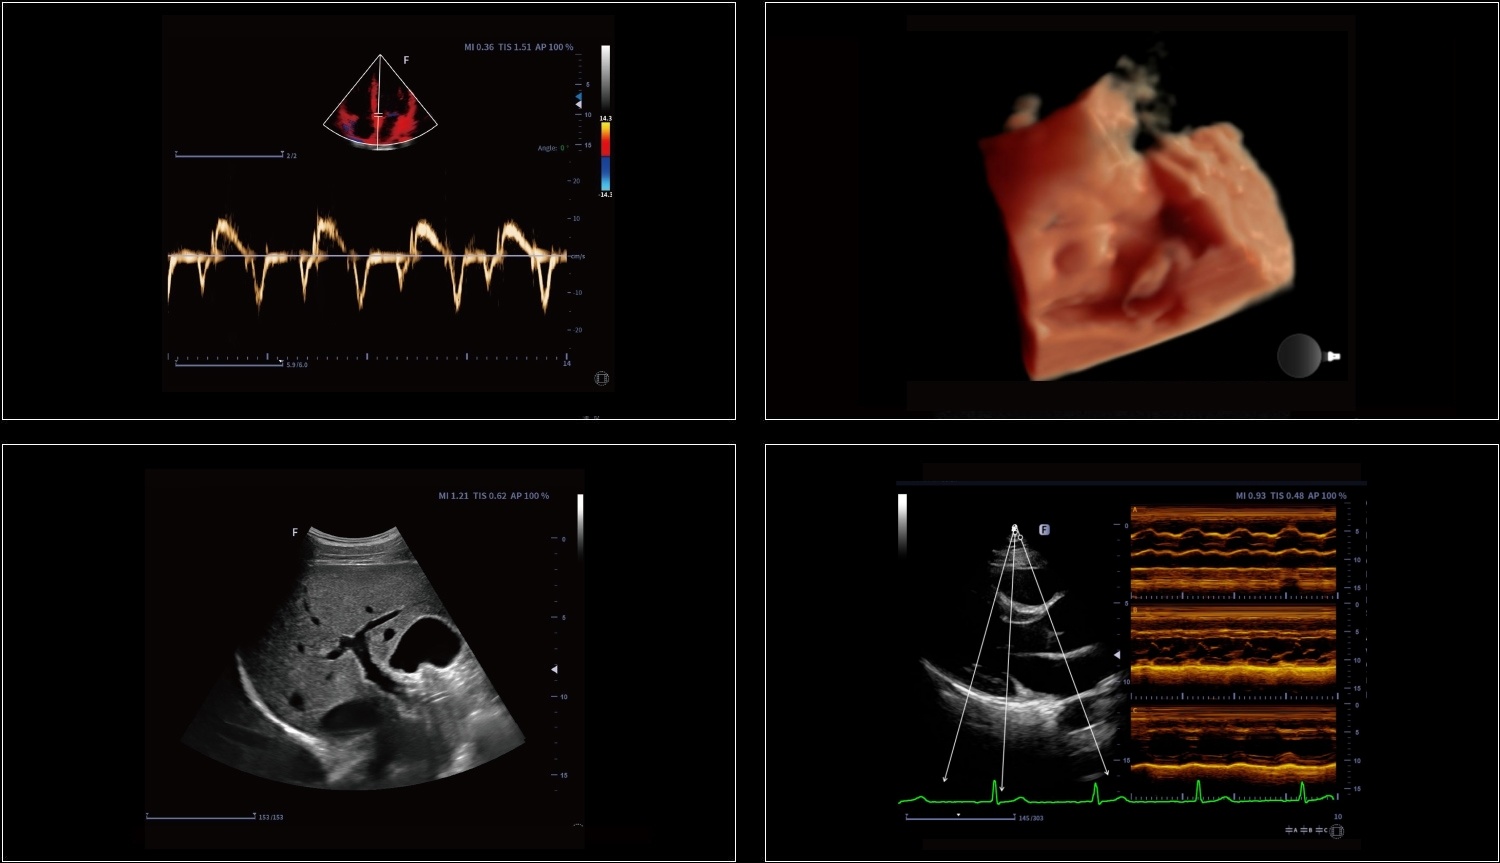

Technologia krzywoliniowego M-Mode (CAM) umożliwia wyświetlanie wszystkich przestrzennych i czasowych relacji ruchów segmentów mięśnia sercowego podczas cyklu sercowego w sektorze skanowania. Zapewnia to nową metodę pomiaru do ilościowej analizy zaburzeń ruchów segmentów mięśnia sercowego podczas fazy skurczowej lub rozkurczowej.

Obrazowanie tkankowe metodą Dopplera (TDI) to solidne i powtarzalne narzędzie echokardiograficzne, które wykorzystuje efekt Dopplera do oceny charakterystyk ściany mięśniowej w całym cyklu sercowym, obejmując prędkość, przemieszczenie, deformację oraz timing zdarzeń. Pozwala na ilościową ocenę zarówno globalnej, jak i regionalnej funkcji oraz timing zdarzeń miokardialnych.